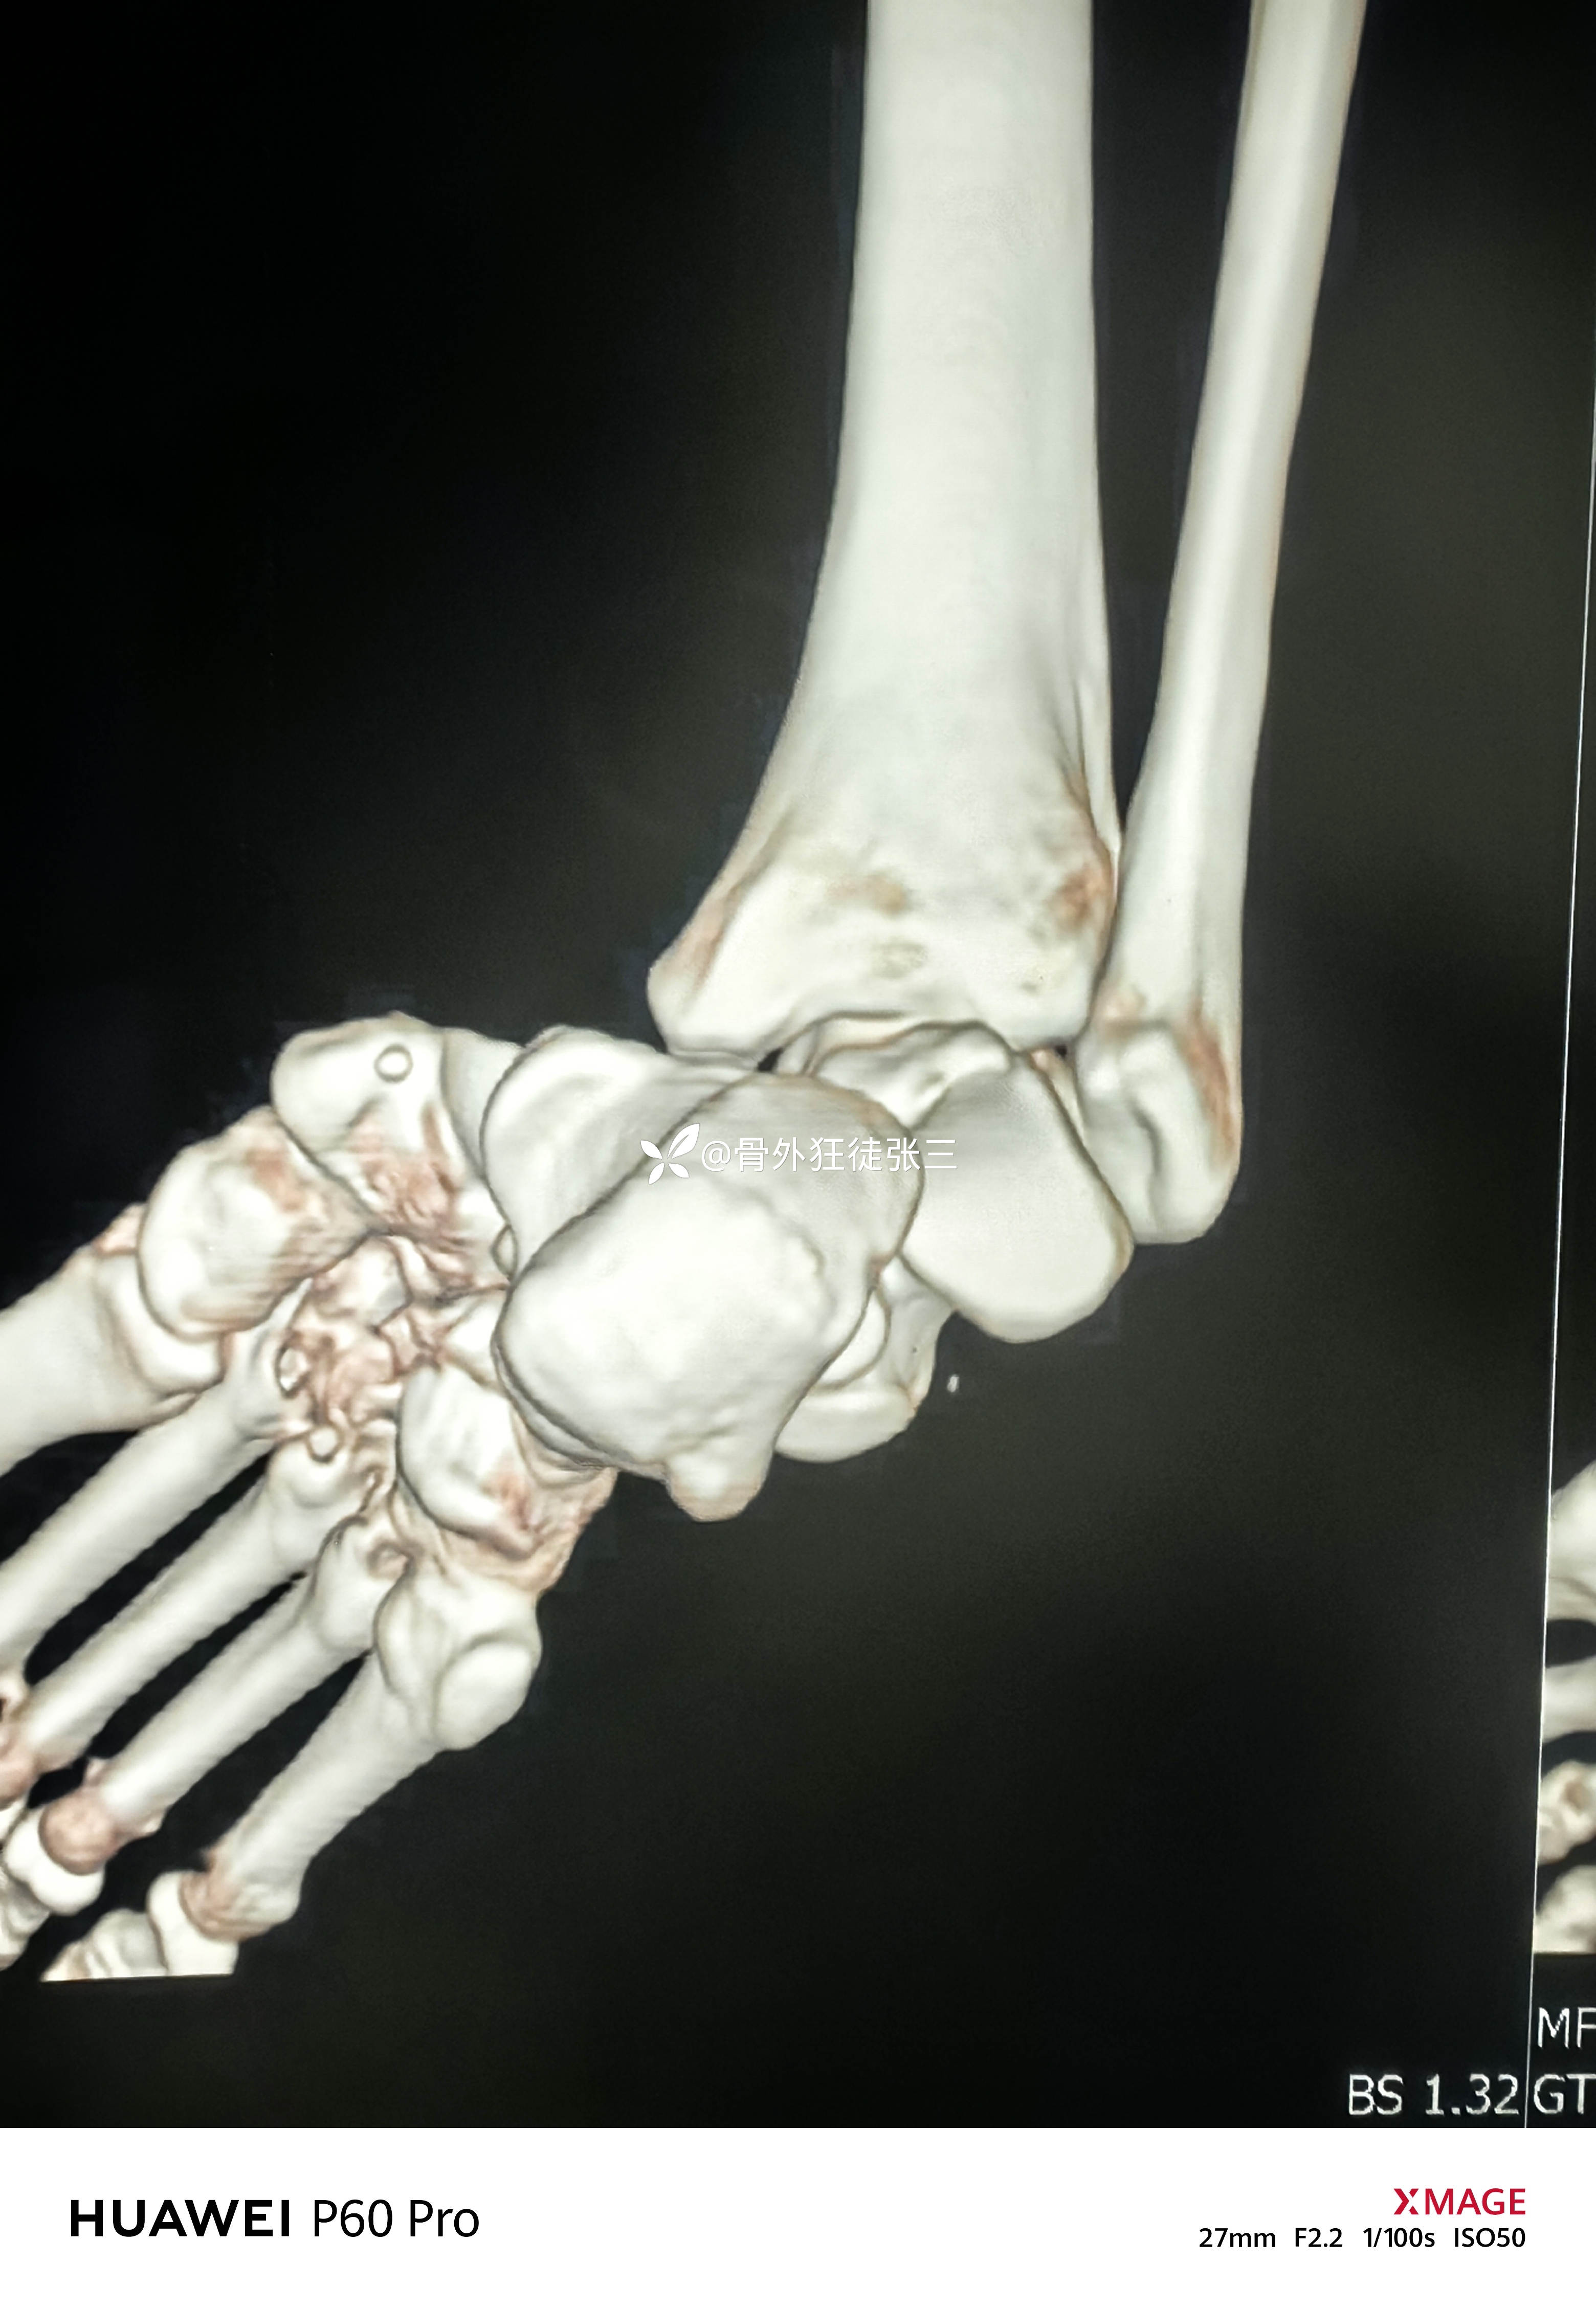

罕见损伤:距下关节脱位

主诉:车祸扭伤右踝关节致肿痛、畸形、活动受限1小时。

辅助检查:

右距下关节脱位(内侧型)